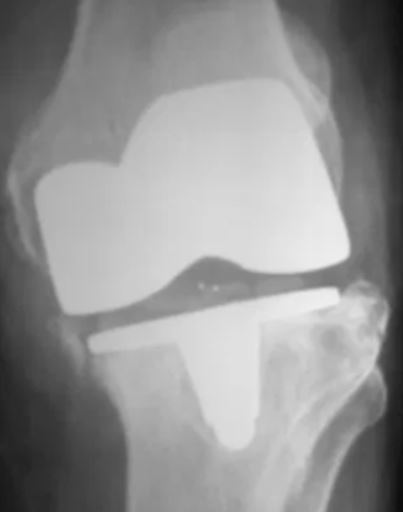

X-rays can detect loosening and osteolysis (bone erosion), as well as component wear, fracture, and malposition.

Wear and Loosening: Friction caused by the joint surfaces rubbing against each other wears away the surfaces of the implant, creating tiny particles that accumulate around the joint. In a process called aseptic (non-infected) loosening, the bond of the implant to the bone is destroyed by the body's attempt to digest the wear particles.

When a knee replacement fails, treatment depends on the cause of failure. Each case is unique and if there is more than the usual amount of bone loss extra pieces of metal or bone are added during revision knee replacement.